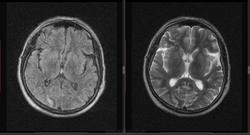

Мужчина 1964 г.р. Жалобы на нарушение памяти, снижение зрения и кратковременную потерю сознания, температура нормальная.

Я думаю что это может быть какой нибудь васкулит, либо Posterior Reversible Encephalopathy Syndrome, о чем можно думать в данном случае?

Контраста нет. Дайком тут!

eto pres

Я представлял синдром с более выраженным изменением сигнала от белого вещества и меньшим - коры.